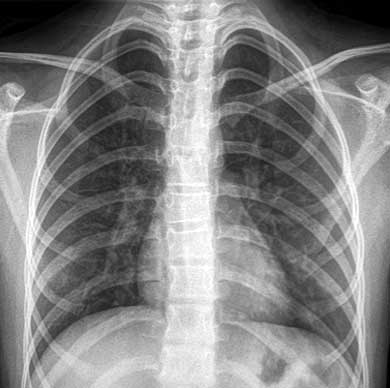

Fue hospitalizada en el servicio de Pediatría, donde se realizaron los siguientes estudios. Perfil inmunológico: factor reumatoide 2.67 UI/mL, velocidad de sedimentación globular 12 mm/h, anticuerpos anti-DNA doble cadena con resultado negativo, anticuerpos antinucleares negativos, complemento C3 93.6 mg/dL, complemento C4 29.9 mg/dL. Perfil infeccioso: anticuerpos IgG e IgM citomegalovirus negativos, anticuerpos IgG e IgM toxoplasma negativos. Radiografía de tórax simple: campos pleuropulmonares y ramas pulmonares normales, sin cardiomegalia o masas ocupativas (figura 1). Radiografía de abdomen simple: aire en cámara gástrica, de escasa cantidad en colon y recto; colon descendente y recto sigmoides con imágenes sugestivas de fecalitos (figura 2). Ultrasonido de hígado y vías biliares: páncreas en situación habitual, con bordes regulares bien delimitados, cabeza y cola dentro de los parámetros normales, cuerpo aumentado de tamaño, en forma de herradura, sin evidencia de líquido peripancreático; hígado y vesícula biliar conservados (figura 3).